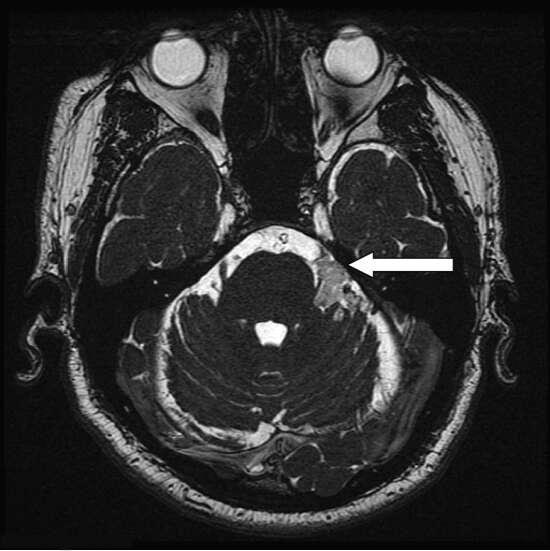

MRI protocol for trigeminal neuralgia is a group of MRI sequences which are put together to best address a possible cause for the condition like pressure on the trigeminal nerve.

• To diagnose an enlarged looping artery or vein pressing on the trigeminal nerve at the cerebellopontine angle.

• To diagnose cerebellopontine tumours.

3D FIESTA

Localized MRA